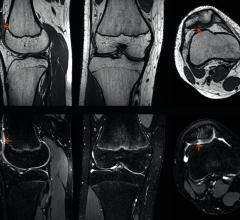

The U.S. Food and Drug Administration (FDA) has cleared GOKnee3D, a magnetic resonance imaging (MRI) application from Siemens Healthineers that significantly reduces the time required to perform comprehensive diagnostic exams of the knee.